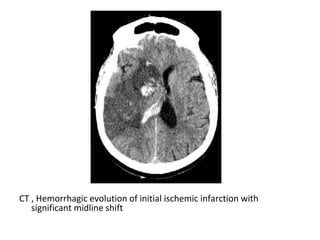

c) Hemorrhage :

-Frank hemorrhage into an arterial infarct

typically occurs a few days after the initial

stroke

-If there is hemorrhage within an infarct from

the outset , a venous stroke or arterial

embolus should be considered

-Hemorrhagic transformation with foci of hemorrhage

at the right post central gyrus

CT , Hemorrhagic evolution of initial ischemic infarction with

significant midline shift